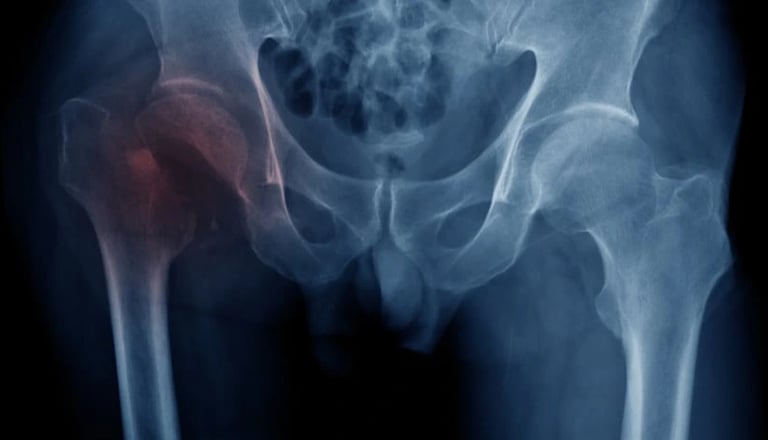

Avulsion fracture

Avulsion fractures happen when a bone fragment separates from the rest of the bone. In children, they are most common in sports like soccer, football, gymnastics, and other sports that involve sudden changes in direction, leaping, and kicking.